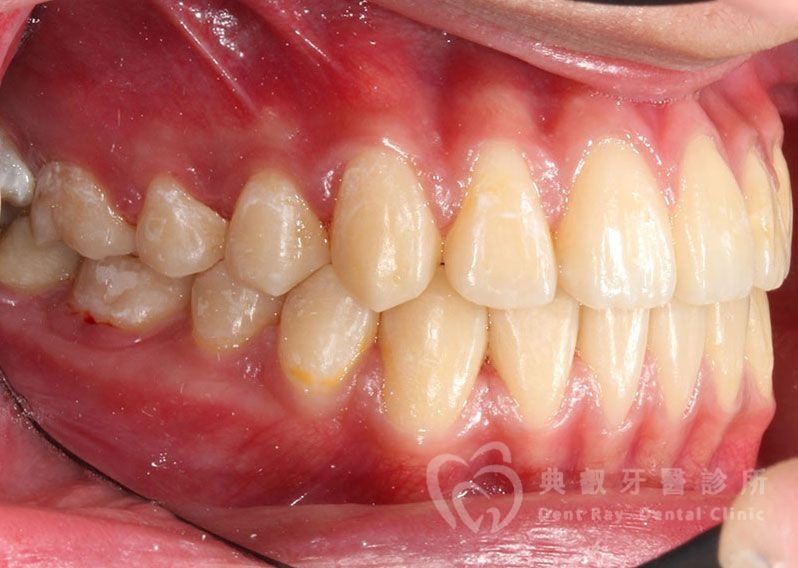

Before

After